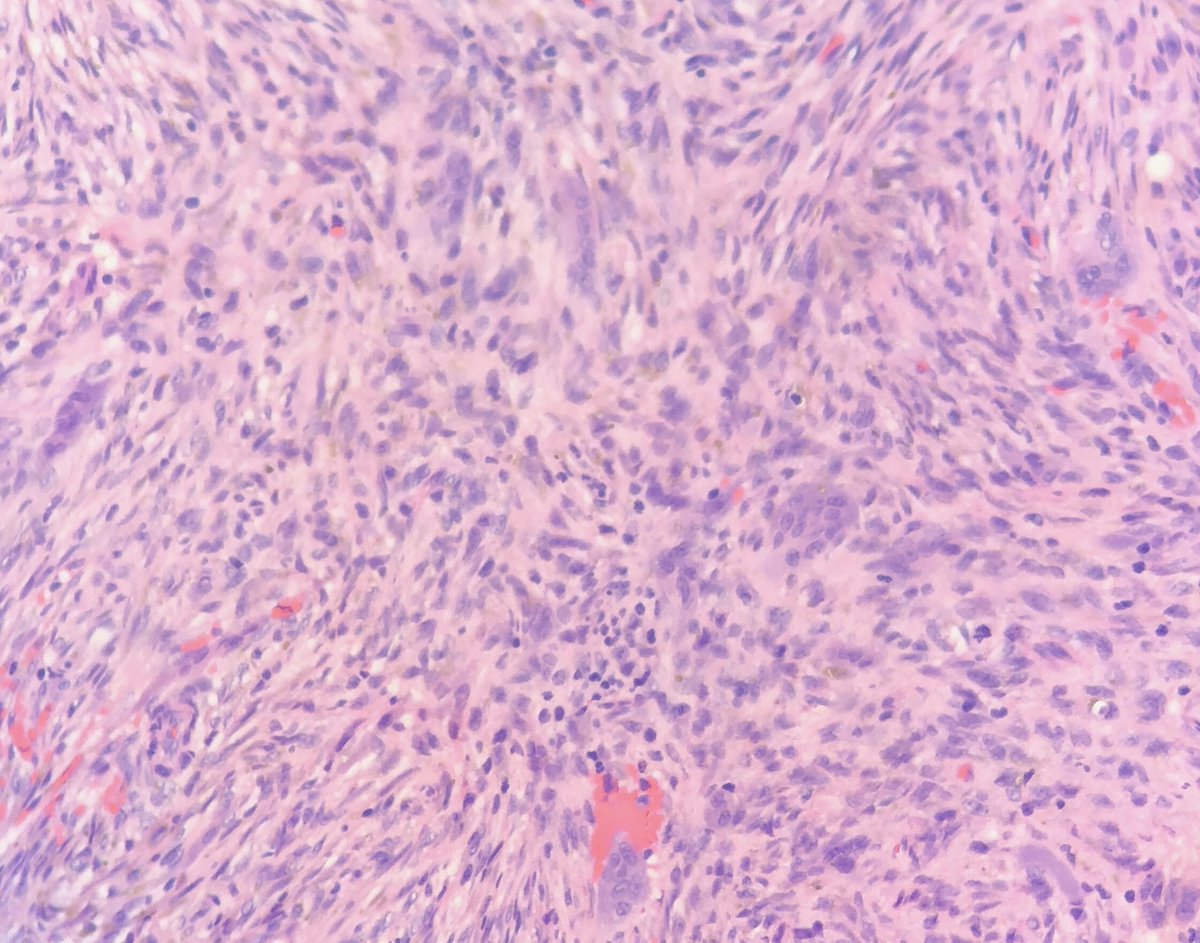

@DownstatePath - Denosumab-treated giant cell tumor of bone. - Characterized by giant cell depletion and new bone formation, having little morphologic resemblance to its pretreatment counterpart (see below).#pathology#pathologytwitter#BSTpath

pic.twitter.com/P3wogh2Gwd